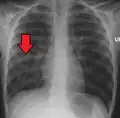

Right middle lobe pneumonia in a child as seen on plain X-ray